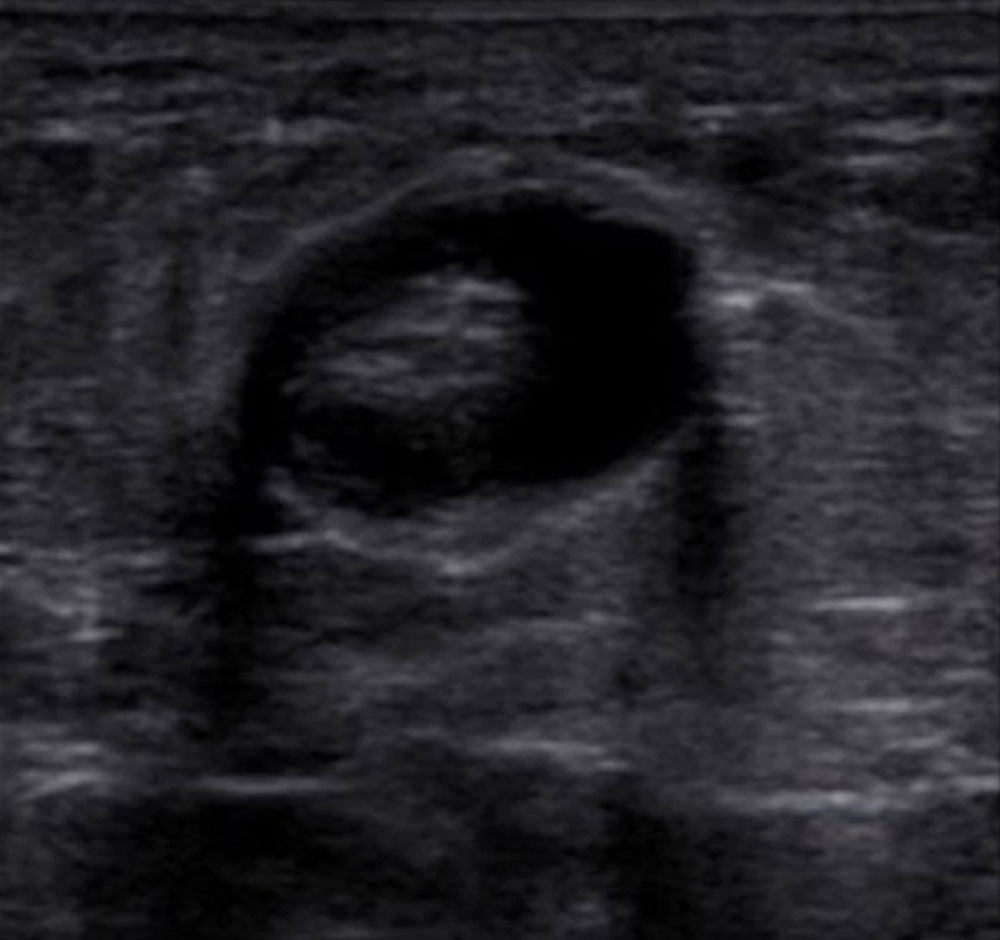

The most important imaging to detect or exclude phlebothrombosis is sonography. The affected vein section shows the thrombus contained in the vessel lumen, which cannot be compressed by compressing the vein with the transducer. Depending on age, this vascular thrombus tends to have a relatively low echogenicity initially in acute cases. The vein diameter is significantly increased by the intraluminal thrombus in the acute phase. In color-coded duplex sonography (CCDS), no color signal is found in the vein owing to the lack of blood flow, even at very low PRF settings (low pulse repetition frequency PRF = high detection sensitivity for flowing blood). With increasing thrombus age, the thrombus shrinks in size and becomes increasingly echogenic. In the further course, at least partial recanalization of the thrombosed vein occurs in favorable cases. Often beginning at the vein wall, blood (echo-free on ultrasound) again flows through the vessel surrounding the thrombus.